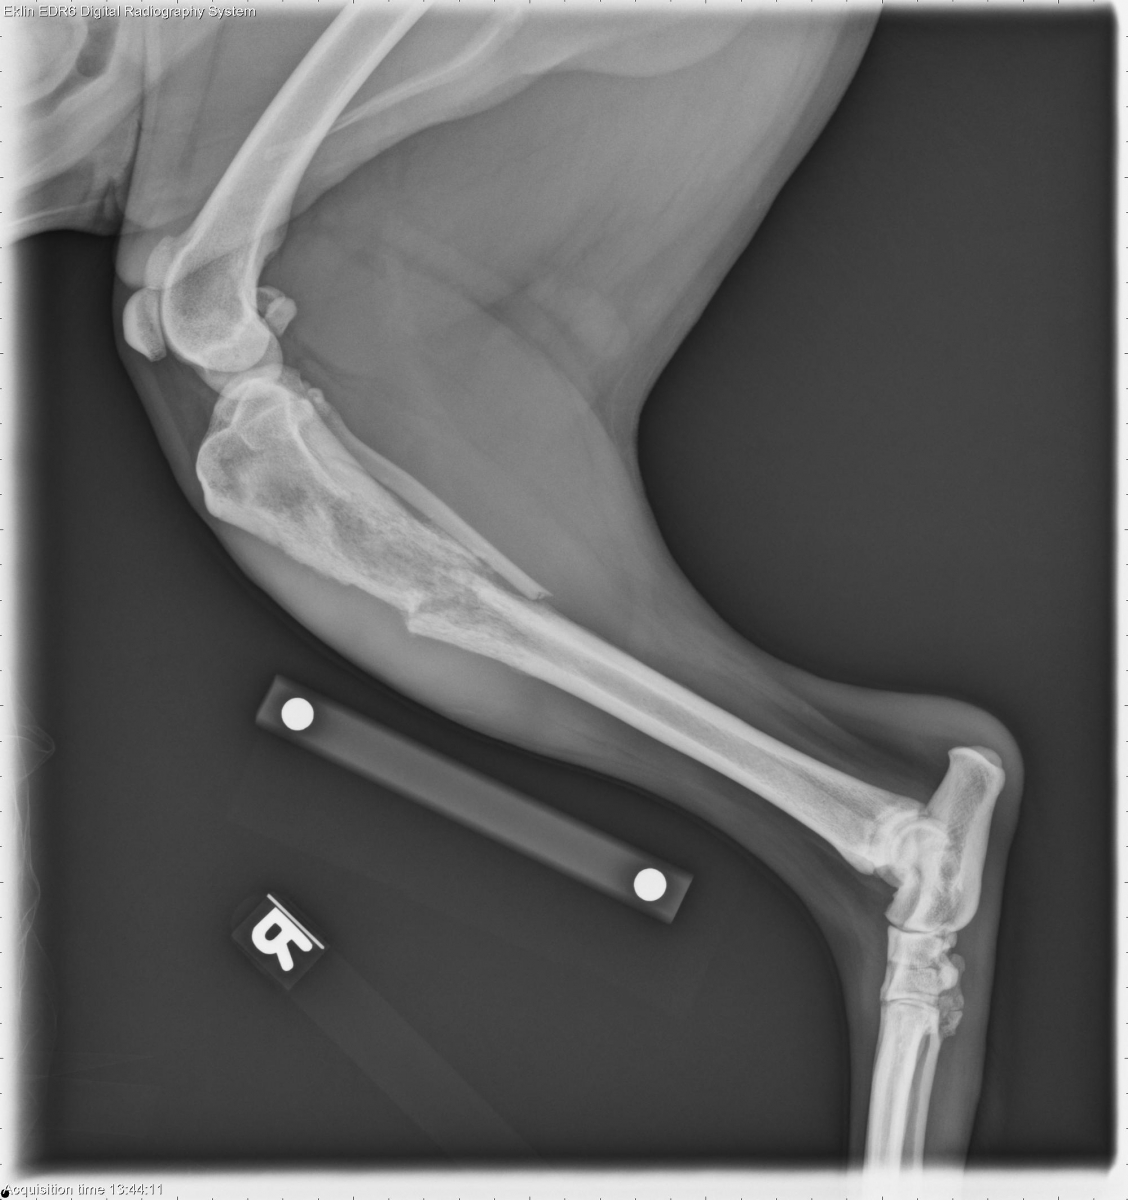

Today’s case is a 4-year-old male neutered Labrador cross. Acute onset of right pelvic limb lameness while playing with a ball. What are your differential diagnoses?

R LAT Hind

There is permeative osteolysis of the proximal third of the tibial diaphysis. There is a short zone of transition and mild irregular periosteal reaction. There is a short oblique fracture through the tibial diaphysis with several small associated fragments. There is mild medial and proximal displacement of the distal segment. A transverse fracture of the fibula is present at the same level.

Aggressive bone lesion with pathologic fracture of the tibia and secondary fracture of the fibula. Differential diagnoses include metastatic neoplasia, fungal osteomyelitis, and primary bone tumor. The location is unusual for a primary bone tumor such as osteosarcoma.

Osteosarcoma with pathologic fracture was diagnosed on cytology after ultrasound guided fine needle aspirate.